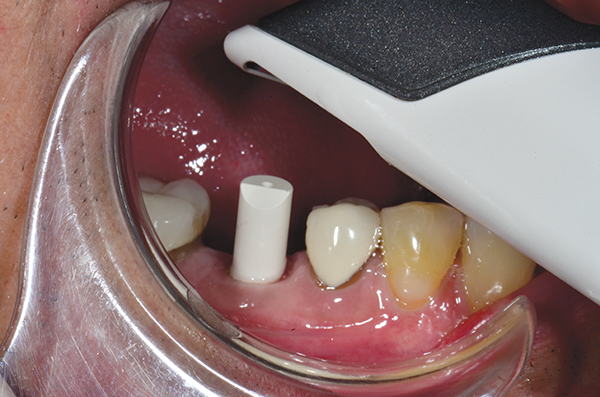

A mandibular right first molar was extracted due to an advanced Class III furcation and an irreversible pulpitis—a combination lesion. An immediate implant placement protocol was elected, and a PEEK abutment was placed on the implant (Figure 1). After 3 months of healing, a scan body was placed on the osseointegrated implant (Figure 2 and Figure 3), and an intraoral scan was taken (TRIOS Pod) (Figure 4) for the fabrication of a screw-retained crown.

Fig 3. Confirmation of seating of scan body.

Figure 3